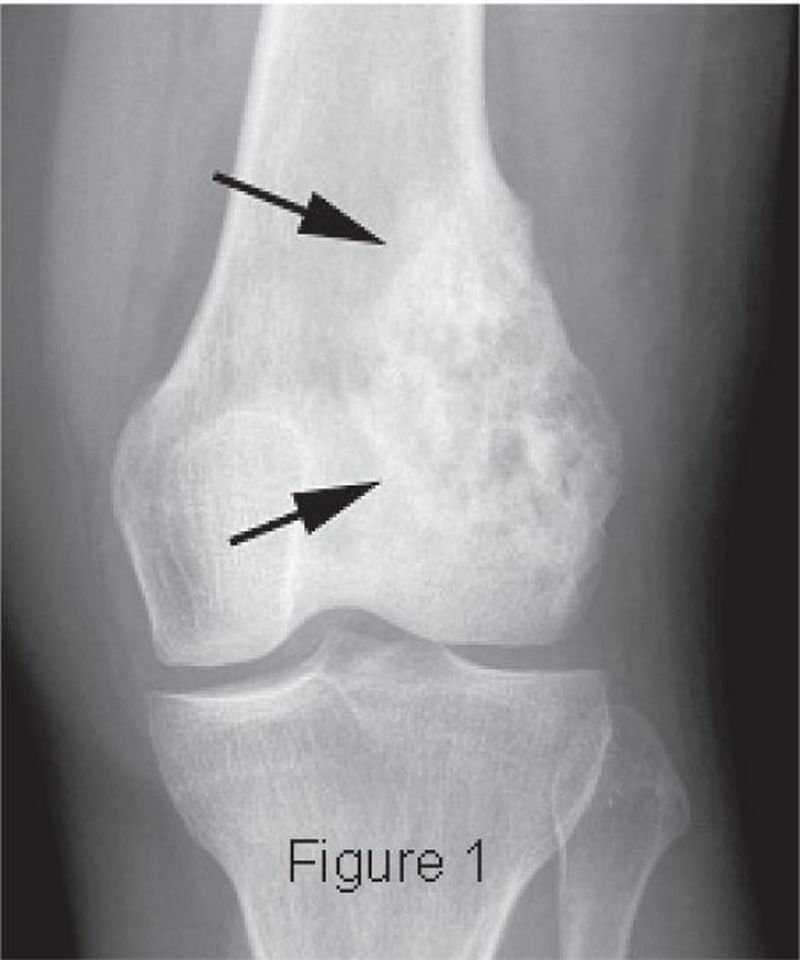

Sunray appearance, codman triangle

Osteosarcoma